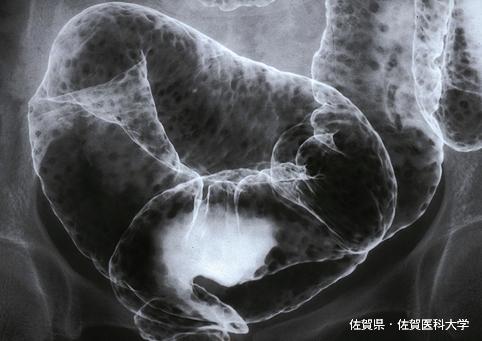

대장 용종증의 형태를 보인 성인T세포 백혈병 (adult T-cell leukemia : ATL)의 일례 (증례제시:사가의과대학, Dr.미즈구치)

Saga Pref., 佐賀医科大学 (Dr.水口)

악성 림프계종양 및 혈액계종양/ATL(성인 T세포백혈병)

대장/S상

X-P

1~9

유(동시성)